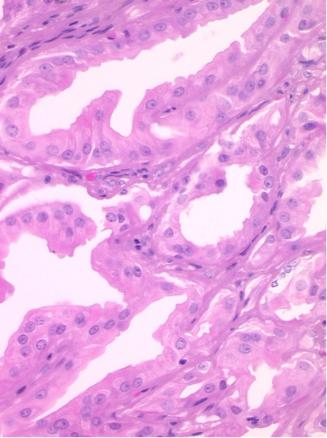

L’hidradénome papillifère est une tumeur kystique bénigne des glandes apocrines. Il est situé dans le derme profond, sans connexion avec l’épiderme. Il survient quasi exclusivement chez la femme d’âge moyen. La localisation habituelle est périnéovulvaire (fig. 2) ; beaucoup plus rarement, elle peut être anale ou périanale.

L’hidradénome papillifère est habituellement asymptomatique ; de rares douleurs et/ou saignements peuvent survenir en cas d’érosion de la surface. Le plus souvent, il prend l’aspect d’un nodule intradermique rond, unique, ferme, mobile, recouvert par une peau normale, de couleur rose, translucide, généralement de petite taille. Parfois, il a un aspect bleuté, exophytique et/ou ulcéré. Le diagnostic repose sur l’analyse histologique (fig. 3).